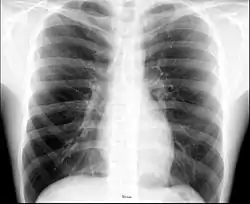

![]() Surface projections of the organs of the trunk, with the thorax or chest region seen stretching down to approximately the end of the oblique lung fissure anteriorly, but more deeply its lower limit rather corresponds to the upper border of the liver. | |